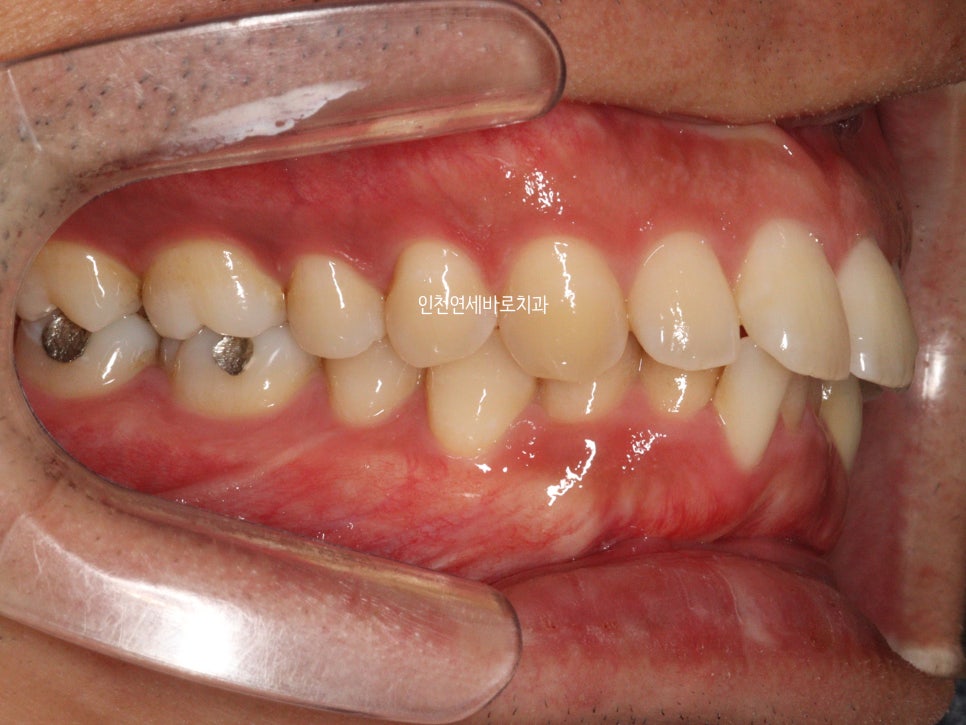

앞니가 뻗쳐있고, 아래치아가 안보이고

덧니가 심해서 내원한 환자분입니다

치료 전과 후의 비교입니다.